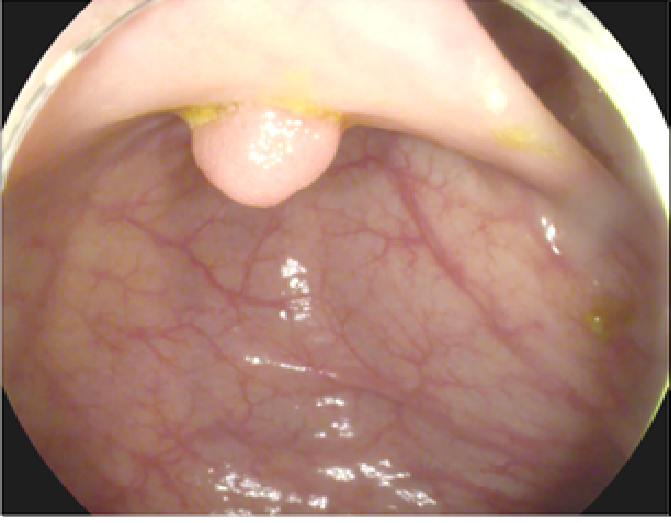

The study used a publicly available dataset of polyp-frames obtained from the ETIS-Larib database [34], containing 196 polyp images. These images were obtained from 34 different colonoscopy videos of 44 different polyps with various appearances and sizes, having a resolution of pixels. The ground truth of polyp areas for polyp datasets is determined by expert video endoscopists. A CNN model trained with such a small amount of data is likely to be meaningless and unstable, so data augmentation was performed on the polyp dataset. Data augmentation had to be performed on the colonoscopy images by considering vivid variations. Otherwise over-fitting would have occurred. In a colonoscopy imagery, polyps exhibits large variations in location, color, and scale. Moreover, variations in brightness and definition also occur due varrying the view-point of the camera. Therefore, in addition to photometric distortions and geometric distortions, we also have considered zooming, shearing, and altering brightness as strategies for data augmentation.

For photometric distortions, we controlled brightness and contrast as an enhancement, while blurring by adding noise with a standard deviation of 1.0. Similarly, for geometric distortions, clock-wise rotation of the polyp images with angles of , , and were performed. Zoom-in and zoom-out with zooming parameters such as 30.00% and 10.00% were performed to obtain different scales of polyp images. Lastly, shearing for both the x-axis and the y-axis was performed to shear the images from left to right and top to bottom, respectively. Fig. 4 shows photometric and geometric forms of image augmentation. In this way, we augmented the data set of the ETIS-Larib database from 196 polyp images to 2,156 images, which is more suitable for training the proposed deep CNN model.

The results shown in Fig. 6 are generated using the proposed deep CNN model on the augmented data set. It can be observed that the proposed model shows better polyp detection performance. As illustrated in Fig. 6, polyps within a frame can be identified at multiple positions, and as noted above in this case, the TP for detection is considered to be 1. The proposed deep CNN model performed better than other benchmark results in terms of the performance metrics listed above, as shown in Table. 2 and Fig. 6.